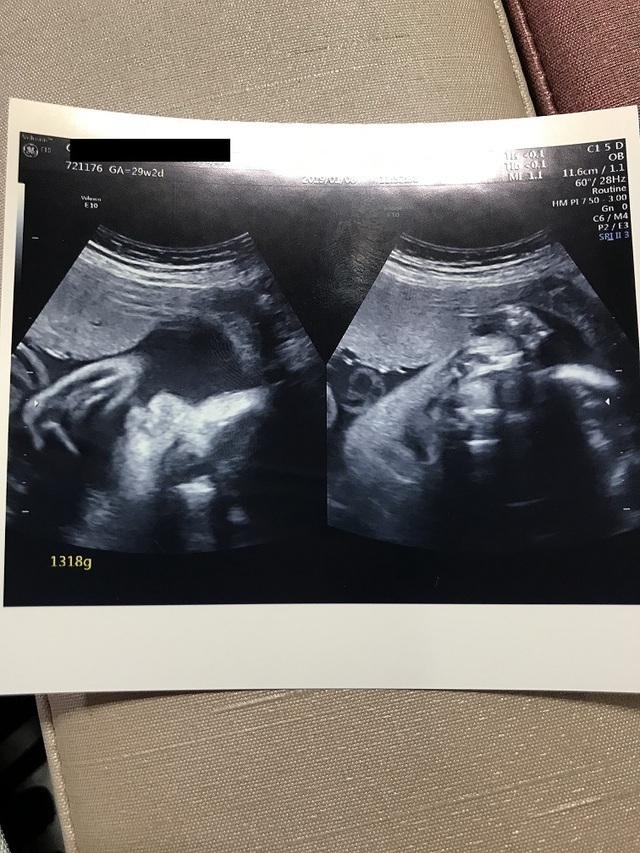

29週2日(29w2d・男の子)|ハニコロ さん(36歳)

エコー写真撮影時のエピソード:

ここ最近とても胎動を感じる日々。

足を伸ばしている様な寝返りをうっている様な(^^)しゃっくりも感じだしてきました。

妊娠後期になり少し屈むのも足の負担になったり、食べた後にムカムカしたり… でも胎動を感じた時には幸せが溢れる日々です。